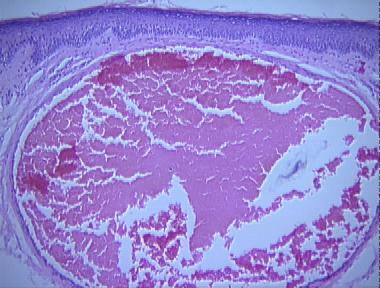

venous lake

Histologic Features